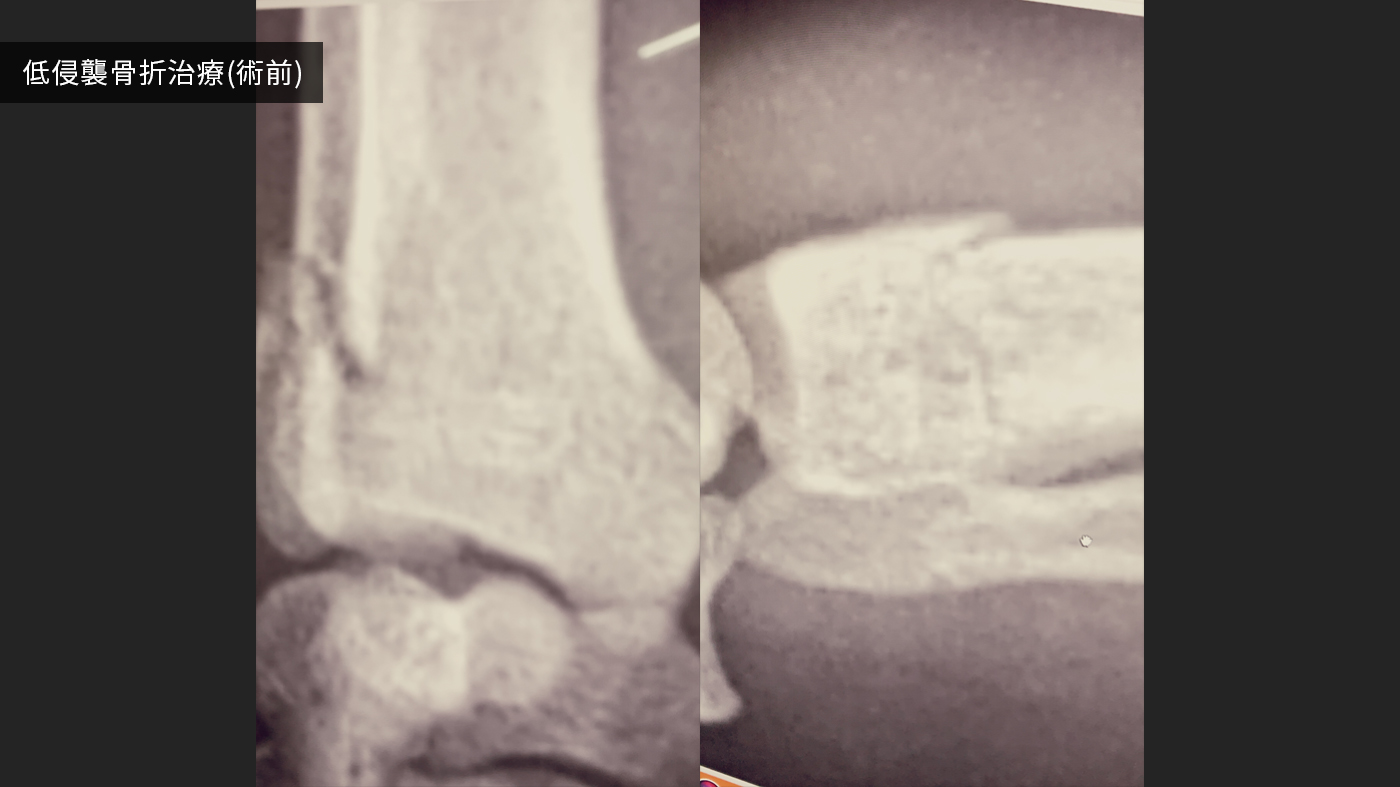

難治性手術症例;股関節全置換術(人工関節)、骨変形に対する矯正骨切り、骨折治療後の癒合不全、前十字靭帯断裂(TPLO,CBLO,mCTWO,mCBLO,頸部椎体固定、胸腰部椎体固定、環軸不安定症固定術)